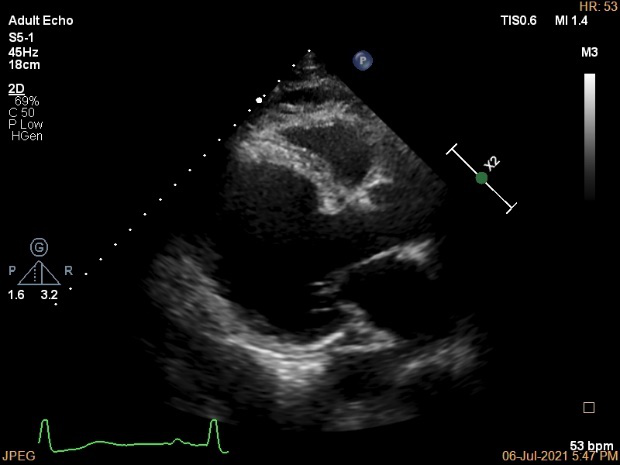

病例四简介

患者为70岁男性,主因“间断胸闷、气短15年,加重1年”入院,患者15年前与活动后出现胸闷、气短症状,无胸痛、心悸,无夜间阵发性呼吸困难及双下肢水肿,1年来上述症状加重,偶有夜间不能平卧。

当地行超声提示:“二尖瓣中-重度关闭不全,射血分数减低”,予药物治疗,上述胸闷、心悸、喘憋症状仍间断出现。10月前因胸痛不缓解,当地医院诊断为“急性心肌梗死”,行球囊扩张术,术后活动仍存在胸闷、气促症状。6月前余当地医院查超声心动:LVEDD74mm,LVEF 31%,二尖瓣重度反流。

入院诊断:

心脏瓣膜病 二尖瓣重度关闭不全 心功能III级(NYHA分级);冠状动脉粥样硬化性心脏病 陈旧性心肌梗死,高血压。

患者老年女性,二尖瓣重度关闭不全诊断明确,患者存在心力衰竭症状及体征,目前经积极药物抗心衰治疗,其心衰症状改善不明显,左室增大,考虑二尖瓣重度关闭不全对患者心功能影响较大,但其二尖瓣置换STS评分15.098%,经综合评估后,认为该患者有行MitraClip指征。